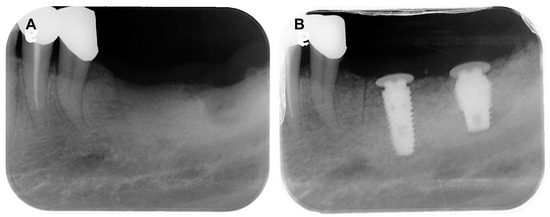

A 78-year-old female patient visited the dental clinic of Daegu Catholic University Medical Center, complaining about a loss of the mandibular left first molar (Figure 1A). The patient had a medical history of hypertension, but she was not taking any medications which needed to be discontinued during the implant procedure. The patient was a non-smoker. For the treatment of choice, it was decided to restore a single implant prosthetic restoration. As a surgical method, flap surgery was planned for bone grafting and implant placement. After the intraoral and radiological examination of the patient, scaling was performed prior to implant placement. The patient received the same pharmacologic protocol of prophylactic oral antibiotics. Amoxicillin sodium (Augmentin; Ilsung pharmaceutical, Seoul, Republic of Korea) with a dosage of 500 mg was to be taken 3 times a day and prescribed routinely, from 1 day before the procedure to 7 days after the procedure. Then, a 4.5 × 10.0 mm implant (AR fixture; Biotem, Seongnam, Republic of Korea) was placed (Figure 1B) with a good initial fixation torque of 40 N/cm2 at placement. After a sufficient healing period of 3 months, the patient received the implant prosthesis.

A 69-year-old female patient visited the dental clinic of Daegu Catholic University Medical Center to restore a missing mandibular left first molar and second molar (Figure 8A). The patient had a medical history of mild diabetes and hypertension, but she was not taking any medications which needed to be discontinued during the implant procedure. The patient was a non-smoker. Through consultation with the patient, it was decided that two implants would be placed. As a surgical method, flap operation was planned for vertical and horizontal bone grafting and implant placement. After the intraoral and radiological examination of the patient, scaling was performed before implant placement. The patient received the same pharmacologic protocol of the patient of case 1. A 4.5 × 10.0 mm and a 5.0 × 8.5 mm implant (AR fixture; Biotem, Seongnam, Republic of Korea) were placed, respectively (Figure 8B). Each implant was placed with the proper initial fixation torque of 30 N/cm2. After a sufficient healing period of 3 months, it was decided the prosthetic treatment procedure would commence.

Figure 1. (A) Pre-operative intraoral periapical radiograph, (B) Post-operative intraoral periapical radiograph.

Figure 8. (A) Pre-operative intraoral periapical radiograph, (B) Post-operative intraoral periapical radiograph.